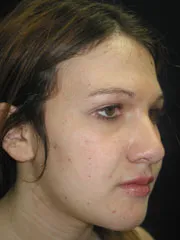

Cheek Implants, Rhinoplasty, Mandibular Advancement, Genioplasty

|

|

|

before |

after |